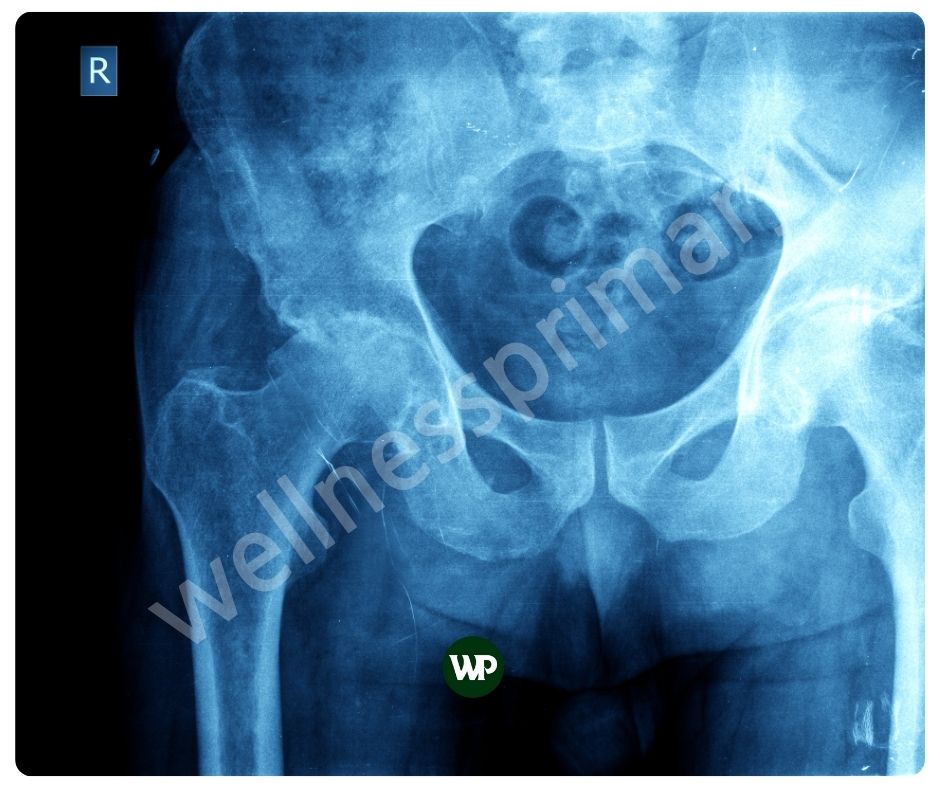

뼈 건강 증진

비타민K2 효능은 칼슘을 뼈에 결합시키는 데 중요한 역할을 합니다. 이는 뼈의 강도와 밀도를 증가시켜 골다공증과 같은 뼈 관련 질환을 예방하는 데 도움이 됩니다. 비타민 K2는 오스테오칼신이라는 단백질을 활성화시켜 칼슘이 뼈에 적절히 축적되도록 합니다. 이는 특히 폐경 후 여성과 노인에게 매우 중요합니다.